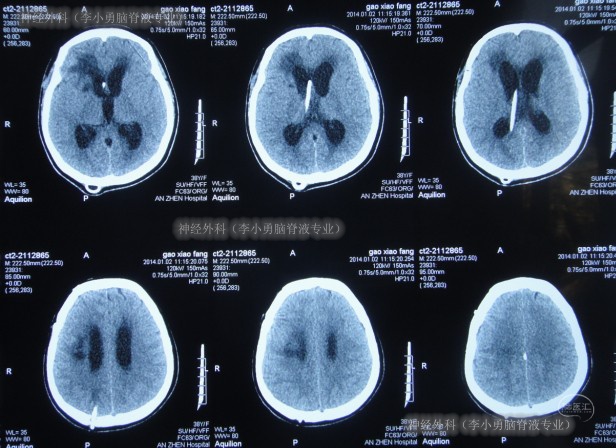

术后当天患者症状就改善为:可简单言语,但因发声细小仍难辨别;经口能进少量流食;查头颅CT示脑室较前缩小,原脑室分流管去除,侧脑室外引流管位置良好(图-14)。

图-14:2014年1月20日术后头颅CT

入院治疗第8天即2014年1月27日,进行了脑室腹壁外引流术(图-16);术后给予将侧脑室外引流管拔除。

图-16:2014年1月27日头颅CT

2014年3月4日(李小勇脑脊液专业治疗44天),出院时:由入院时的反应迟钝,张口困难、不能伸舌、不能经口进食,不能言语,遵命活动动作微小,出院时变得:反应灵敏、张嘴伸舌,饮食,言语,肢体活动均变基本正常。头颅CT示脑室缩小和分流管位置良好(图-18)。

图-18:2014年3月4日出院时

出院后10个月即2015年1月7日,来院复查:身体一直挺好的,已完全投入正常的工作和日常生活;查头颅CT示无异常(图-20)。

图-20:2015年1月7日

出院后10年零7月即2024年10月17日,来院复查;复查时:出院10年余时间里身体一直挺好的,复查头颅CT示无异常(图-21)。

图-21:2024年10月17日〔本典型病例所涉及的图片和视频均经患者本人或家属同意,如有异议,请联系该内容发布方〕